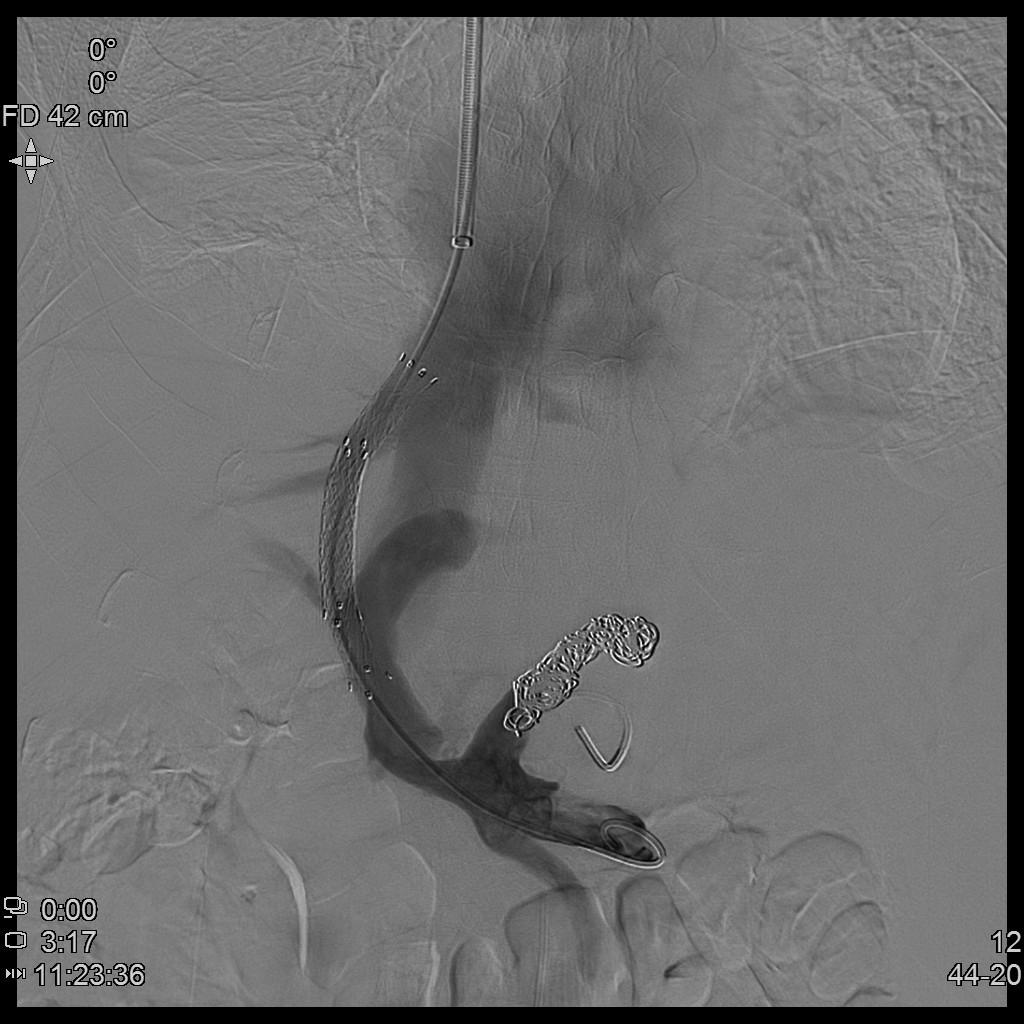

TIPS术示意图

- 成功穿刺到门静脉分叉处,置入猪尾巴导管至脾静脉远端造影显示胃冠状静脉及食管静脉重度迂曲扩张。门静脉压力高达63cm水柱!

- 栓堵曲张的胃冠状静脉及食管静脉。沿穿刺道置入支架建立门-腔分流道,复测门静脉压力即刻降至40cm水柱!

- 术后患者腹水逐步消退、吸收,腹胀症状明显缓解。TIPS术不仅显著降低患者再次消化道大出血风险,同时有效缓解门脉高压性胃病、顽固性腹水等系列门脉高压临床症状,生活质量明显改善。